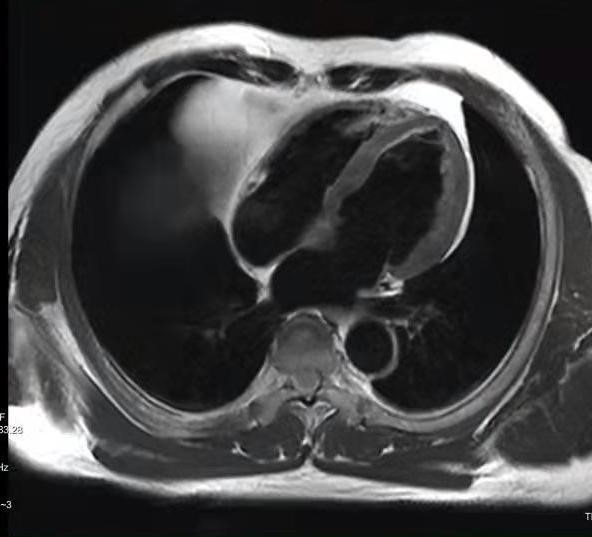

心脏MRI图像示例:

图2. 左室水平长轴四腔位,主要是显示心脏四个心腔以及室间隔、房间隔、二尖瓣、三尖瓣、乳头肌等结构。

图3. 左室短轴位亮血与黑血序列(左图亮血、右图黑血),垂直于左室长轴的层面,主要显示左心室各壁